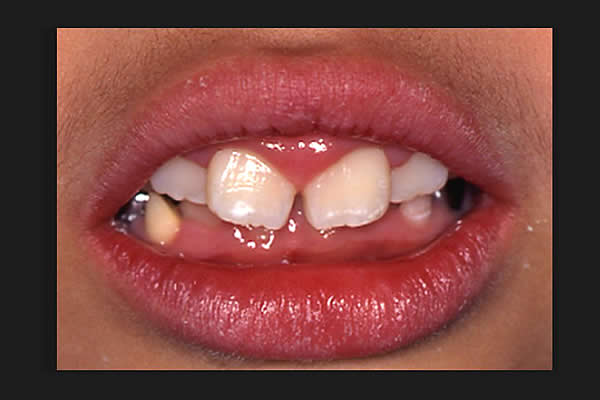

最近、口をポカ~ンとあけている子どもや若者が気になってしかたがない。そんな子どもが以前より増していると思う。口呼吸をしている子どもの口唇は、厚かったり、上唇が山型をしているのですぐわかる。それに、歯肉が硬く腫れている。

(図1)

口呼吸性の歯肉炎

口呼吸性の歯肉炎だ。プラークの付着による歯肉炎とは異なり、歯を磨いても治らない。外気がそのまま、歯肉に当たるので肥厚するのだ。さらに、扁桃腺を見てみると、腫れている子が多い。